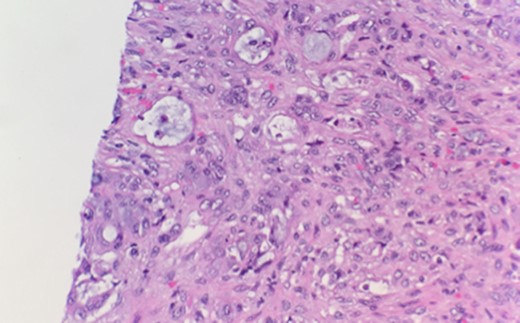

Microscopic examination reveals thickened appendicial wall with infiltrating individual malignant cells (Fig. 1).

High-power examination reveals some malignant cells demonstrating Signet ring cell features (Fig. 2).